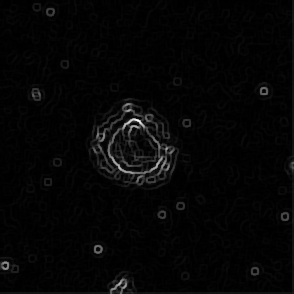

Perimeter values measured with batch sequence processing (without FFT) is results of inflexible filter parameter. Each image may be considered as model object with: background which must be filtered out, cell itself to be segmented and measured. Most people usually recognize cell body surrounded by thin black collar or aureole related to cell lamella (thin sheet of cell membrane protrusions not always recognized by novice user). It may be physically absent due to cell rounding process (Frame 1), when cell detach from substrate. And cell core is refers to cell nuclei zone however it is contain not only nuclei. The core is central part of cell image, it is thicker than lamella which causes contrast difference. If simplify cell shape maybe described as positive meniscus lens (flat part is attached to substrate) with zones of different contrast (caused by presence of cellular structures). Uniformed binary operations cannot provide same level of detection accuracy. Thus proper binarization procedure and filtering operations prior to binarization were determined as important part affecting on segmentation accuracy. However further we find out that binarization procedures cannot be standardized and must be set up for each image. During inspection of image properties false recognition was noticed for images with higher difference of pixel values compared to control. Adjustable FFT (with real time results exhibition) was performed on such images to extract object from background (Fig.10). Filtration with different options of FFT applied on sample image with bad detection accuracy (Frame 9) represented at Fig.11(a-c) show that we can find parameters of filtration providing good level of segmentation. Threshold was adjusted manually for each image.

Refer to caption

Figure 10: Dialog window for FFT filtering and conversion to binary image. Where are D1 and D2 represent the size of filter. Maximum and minimum values is depend on image window. Third option for choice is Threshold value.

(a) Filter settings: D1=280.1423; D2=0.74; threshold=0.04

(b) Filter settings: D1=65.5; D2=0.8688; threshold=0.0305

(c) Filter settings: D1=263.1961; D2=90,7574; threshold=0.0417

(d) Original unprocessed image

(e) Filter option

(f) Filter option

(g) Filter option

(h) Overlay of manually defined perimeter

Figure 11: Filtration process of Frame 9 with manually chosen FFT filter properties(a-c). Results of segmentation (e-g) with manually outlined image(h).

Image (f) of Fig.11 shows most similarity to manually detected cell contour. But it has not connected contour which is considered as false detection. However compared to results after batch processing it has higher accuracy rate.